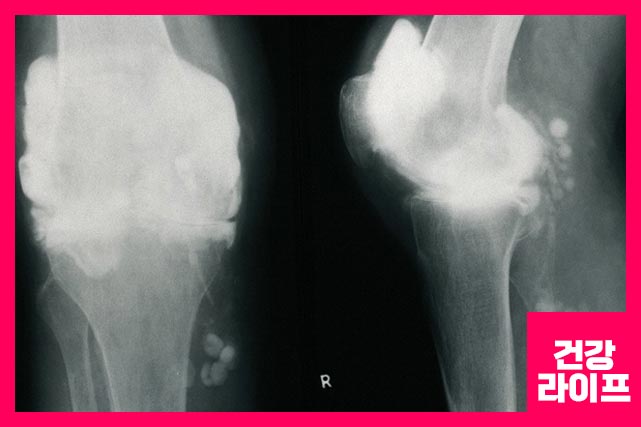

관절에는 얇은 막인 활막으로 둘러싸여 있으며, 관절 활막에 염증 반응이 지속적으로 나타난다면 류마티스 관절염이라고 말합니다.

관절은 뼈와 뼈를 연결하는 곳을 말합니다. 이 곳에 류마티스 관절염이 발생하면 연골 손상, 뼈 침식이 일어나면서 관절에 치명적인 손상이 일어나면서 더 이상 관절 기능을 제대로 할 수 없게 될 수 있습니다.